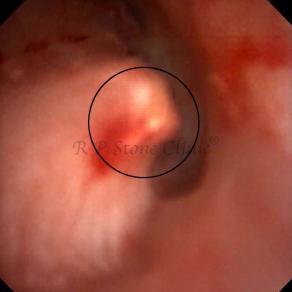

These images are taken as snap shots from the video recording of RIRS Surgery done at our hospital. These are Randall’s Plaques seen with Digital FLEX XC & Digital FLEX XC S. The cream or whitish patches are seen on the tips of RENAL PAPILLAE as seen in images below.

The Below Images Show Small Stones attached to the Renal Papillae.